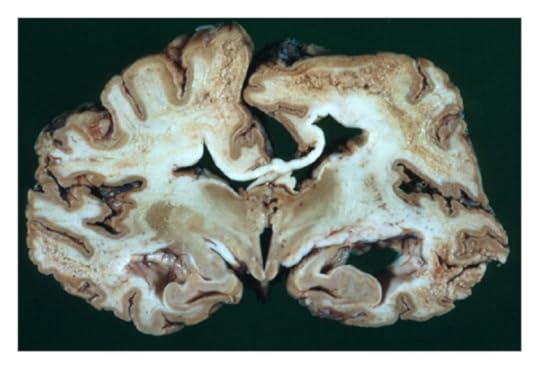

Метаанализ структурных исследований мозга показал, что у людей с СДВГ наблюдается некоторое уменьшение объема мозга по сравнению с контрольной группой. Наиболее выраженные отличия в размере оказались у прилежащего ядра, миндалевидного тела и скорлупы в составе полосатого тела. Речь о структурах, связанных с регулированием и распознаванием эмоций, а также восприятием награды. Но различия эти не катастрофические.

В еще одном исследовании у детей с СДВГ наблюдалась задержка в достижении максимальной толщины коры по сравнению с контрольной группой. Медианный возраст, когда 50% точек коры достигли своего пика, составил 10,5 лет у детей с СДВГ, в то время как у контрольной группы — 7,5 лет. Это укладывается в гипотезу о том, что СДВГ может быть связан с задержкой созревания мозга. Возможно, поэтому некоторым все же удается СДВГ «перерасти». Важно уточнить: это не значит, что при СДВГ кора мозга тоньше – просто пиковая зрелость наступает позже.